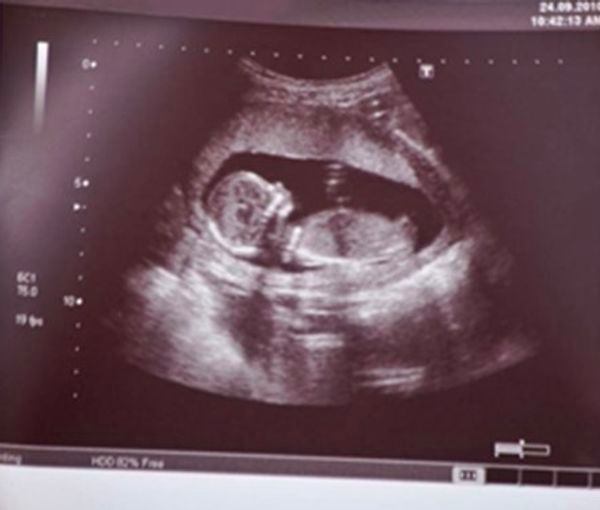

محمد اکرمی، رییس انجمن علمی ژنتیک پزشکی ایران خبر داد که «بر اساس بخشنامه اداره کل تجهیزات پزشکی، واردات و تولید کیت‌های غربالگری ممنوع شده است». هم‌زمان اعلام شد که بر اساس آخرین آمارها در ایران، ۲۰ درصد زوجین دارای مشکل ناباروری هستند.

محمد اکرمی، رییس انجمن علمی ژنتیک پزشکی ایران روز پنج‌شنبه دوم تیر در این زمینه به رسانه‌های داخلی گفت: «چندی پیش بخشنامه‌ای از سوی اداره کل تجهیزات پزشکی ابلاغ شد که بر اساس این بخشنامه هر گونه واردات و تولید کیت‌های غربالگری ممنوع است اما این ابلاغیه بلافاصله با واکنش‌های منفی انجمن‌های علمی مواجه شد.»

او افزود: «به همین دلیل و پس از اعتراضات، در مرحله بعد محتوای بخشنامه ثابت ماند اما عنوان آن تغییر کرد و در حال حاضر در سایت وزارت بهداشت،درمان و آموزش پزشکی، اداره کل تجهیزات پزشکی و سازمان غذا و دارو این بخشنامه موجود است.»

این مقام صنفی درباره علت واکنش‌های منفی نسبت به بخشنامه ممنوعیت واردات و تولید کیت‌های غربالگری گفت: «ایرادی که در حال حاضر به کار وارد است این است که این ممنوعیت با شرایط اکنون کشور که سن ازدواج و به تبع آن سن بارداری افزایش یافته، همخوان نیست.»

او افزود: «در حال حاضر که هدف کشور حمایت از جوانی جمعیت است، همه باید کمک کنیم این دغدغه‌ای که برای خانواده‌ها در زمینه داشتن فرزند سالم در سن بالای بارداری مادر به وجود آمده، برطرف شود. به همین علت به شدت نسبت به این بخشنامه واکنش منفی نشان داده شده است.»

رییس انجمن علمی ژنتیک پزشکی ایران درباره تاثیر ممنوعیت واردات کیت‌های غربالگری بر افزایش جمعیت کشور نیز گفت: «ممنوعیت واردات این کیت‌ها مانع افزایش جمعیت در کشور شده و مردم نمی‌توانند با اطمینان خاطر تصمیم به باردار شدن بگیرند.»